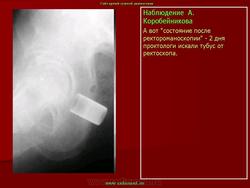

Инородные тела